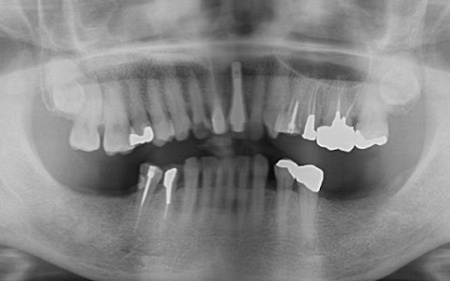

拝見したところ、左上奥歯2本(第1小臼歯、第2小臼歯)の被せ物が外れていたため、レントゲン撮影で詳しく検査をした結果、歯根が折れていることが確認できました。

また、以前歯の神経を除去する根管治療を受けたそうですが、その際に使用された細い器具 (リーマー)の破片が根管内に残っています。

さらに、歯の周囲にある歯周ポケットの深さを測定したところ、口蓋側(上顎の内側)は歯根の先端まで達していました。

これでは、再度根管治療を行っても歯茎の状態が改善する可能性は低いと考えられます。

このまま放置すると周囲の骨や歯茎に炎症が広がるリスクがあるため、早急に適切な治療をする必要があると診断しました。